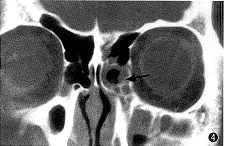

图4 左侧额窦、前组筛窦和上颌窦炎,炎症波及左鼻丘(

)

本组30例慢性鼻窦炎53侧(7例为1侧发病)中均有不同程度的前组鼻窦炎。其中额窦、前组筛窦和上颌窦炎17侧,炎症波及鼻丘者10侧(图4);前组筛窦和上颌窦炎16侧,炎症波及鼻丘者12侧;额窦炎2侧,均伴有鼻丘炎症;前组筛窦炎5侧,鼻丘正常;上颌窦炎13侧,炎症波及鼻丘者1侧。炎症波及鼻丘者共25侧,占47. 2%(25/53)。此外,鼻丘骨质增厚者6例;单气房发病18侧,双气房以上发病7例。高、中、低位鼻丘的发病分别为8/64、7/64、10/74侧。